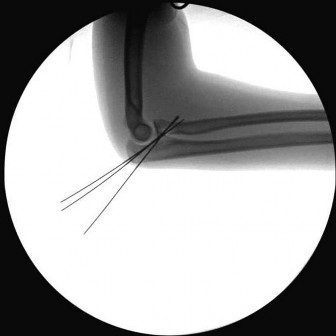

Question 13:

A 6-year-old boy sustains a severe extension-type supracondylar humerus fracture after a fall. Radiographs classify it as a Gartland Type III. The distal fragment is severely displaced posteromedially relative to the proximal shaft. Based on this specific displacement pattern, which of the following nerve structures is at greatest risk of tethering or injury from the proximal fragment?

Correct Answer: Radial nerve

Explanation:

In an extension-type supracondylar humerus fracture, the displacement of the distal fragment dictates the direction of the proximal spike. If the distal fragment is displaced posteromedially, the sharp proximal fragment is thrust anterolaterally, placing the radial nerve at the highest risk of injury. Conversely, if the distal fragment displaces posterolaterally, the proximal spike goes anteromedially, placing the median nerve (and AIN) at greatest risk.